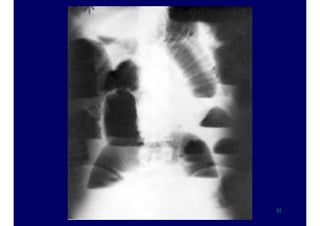

X-ray evaluation

upright PA and lateral film of the chest

supine and erect plain film of the

abdomen

–the upright film should include the

diaphragm

 to detect free intraperitoneal

air

 only horizontal beam films detect

fluid levels within the bowel